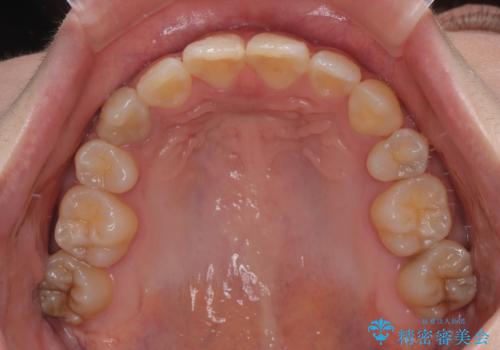

- 上下の八重歯を気にして来院された患者様です。

非抜歯矯正で歯列を整えると、治療後に口元が今よりも突出する可能性が高かったため、上下左右の小臼歯4本を抜歯し、ワイヤー装置にて矯正治療を行うこととしました。

右上の八重歯の影響で、右側は上顎歯列が前方位の咬み合わせとなってしまっていたため、上顎は第一小臼歯を、下顎は第二小臼歯を抜歯することで咬み合わせや上下正中を調整することとしました。

第二小臼歯抜歯の治療となったため、やや時間はかかりましたが、概ね予想通りの期間で治療を終えることができました。